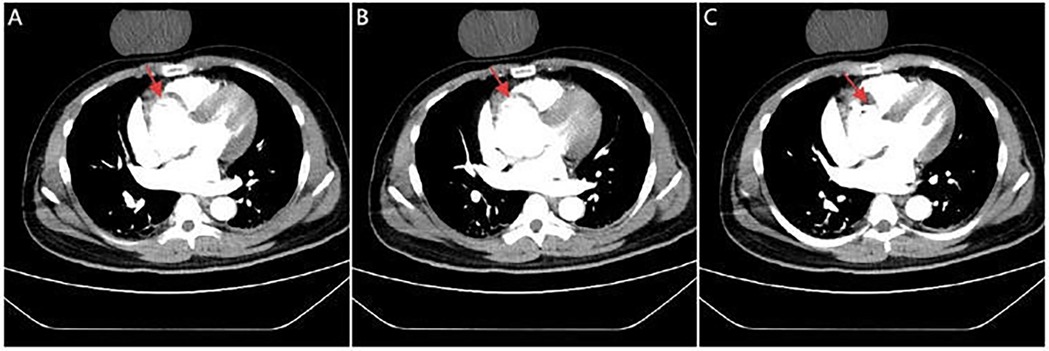

Figure 2

CTA images. Serial CTA images (A–C) show located right coronary sinus of valsava dissection (red arrow).

A 42-year-old man with no known comorbidities and a family history of AD presented with sudden-onset chest pain during esports gameplay. ECG showed inferior STEMI with complete heart block (Figure 1A). CAG revealed a normal left coronary system, but the RCA could not be engaged. Aortic root angiography showed no anomalous origin of the RCA; however, it suggested a possible dissection of the right SOV (Figures 1B–D; Supplementary Video 1). CTA revealed ascending aortic dilation and a localized dissection of the right SOV (Figures 2A–C; Supplementary Video 2). The emergency transthoracic echocardiography (TTE) revealed dilation of the ascending aorta, measuring 43 mm in diameter. Despite the recommendation for immediate surgery, family hesitation delayed intervention. The operative findings showed that a dissection of SOV extending into the RCA ostium. Coronary artery bypass grafting (CABG) and sinus reconstruction were performed, however the patient developed cardiogenic shock and refractory ventricular arrhythmias. The family declined mechanical circulatory support (MCS), and the patient subsequently died.

In our first case, the patient was obese, had a family history of AD, and experienced emotional stress prior to symptom onset. Aortic intimal flap obstruction of the RCA ostium led to failed catheter engagement and precluded PCI (20). Emergent CTA confirmed right SOV dissection, representing an absolute indication for emergency surgery. Unfortunately, the patient died after CABG and sinus reconstruction due to recurrent malignant arrhythmias and refractory cardiogenic shock. The poor outcome was multifactorial, involving a nondominant left circumflex artery with right-dominant circulation, prolonged vessel occlusion causing extensive myocardial necrosis, delayed diagnosis, family hesitation delaying intervention, and refusal of postoperative MCS (21).